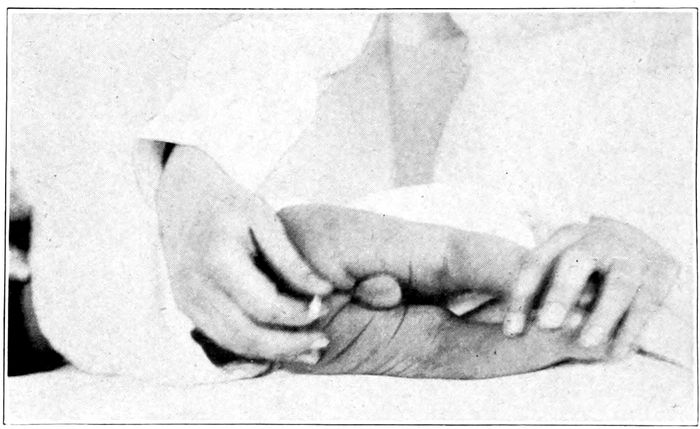

| 98. |

Measuring the diagonal conjugate with the finger |

219 |